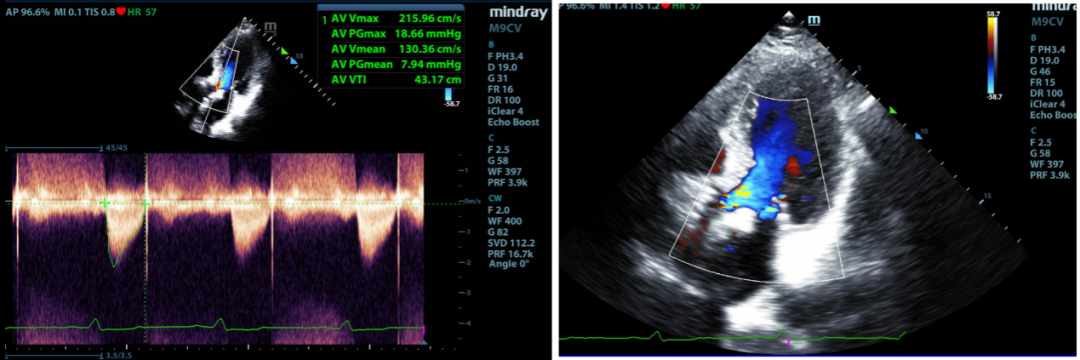

在手术进行之前,心内科团队与多方专家进行会诊沟通,认为患者钙化明显,冠脉需要介入处理,故需要选择一款过弓顺利、支撑力优良,不影响后期冠脉手术的瓣膜。患者术后即刻食道超声可见支架位置固定良好,短轴塑性良好,支架扩张形态均匀一致,瓣叶启闭运动尚可;EF提高到60%,最大峰值血流速为1.7m/s,平均跨瓣压差为7mmHg,瓣口面积约为2.2cm²,瓣环内未见明显反流,瓣架前后缘微量瓣周漏。患者心功能明显改善,恢复状态良好,手术圆满成功。

术后第六天出院前,心脏彩超提示:人工瓣支架位置固定良好,短轴塑性良好,支架扩张形态均匀一致,瓣叶启闭运动尚可;EF为55%,最大峰值血流速为2.53m/s,平均跨瓣压差为13mmHg,瓣口面积约为2.0cm²,瓣环内未见明显反流,瓣架前后缘探及微量瓣周漏。

术后30天随访,心脏彩超提示:人工瓣支架位置固定良好,短轴塑性良好,支架扩张形态均匀一致,瓣叶启闭运动尚可;EF为59%,最大峰值血流速为2.18m/s,平均跨瓣压差为10mmHg,瓣口面积约为2.0cm²,瓣环内未见明显反流,瓣架前后缘探及微量瓣周漏。

本次患者完成术后一年随访,心脏彩超提示:人工瓣支架位置固定良好,短轴塑性良好,支架扩张形态均匀一致,瓣叶启闭运动尚可,闭合欠佳;EF为55%,最大峰值血流速为2.15m/s,平均跨瓣压差为8mmHg,瓣口面积约为1.9cm²,瓣环内未见明显反流,瓣架前后缘探及少量瓣周漏。

患者术前基线时、术后即刻及术后随访结果如下:

从随访结果可见,人工主动脉瓣膜植入术后即刻至术后一年无明显变化,瓣膜位置固定正确,瓣架展开充分,瓣叶运动状态可,瓣膜功能良好,对患者心功能有着持续性的改善。此次术后一年随访结果优秀,说明SinoCrown™瓣膜的长期临床疗效值得肯定和进一步期待。